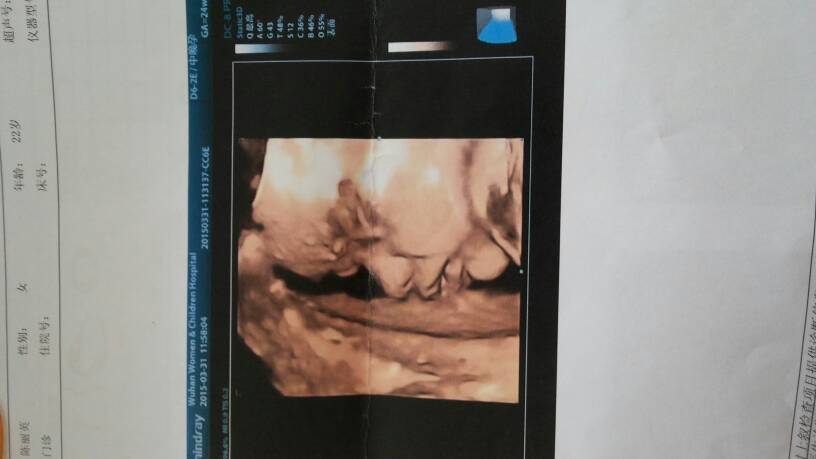

做四维医生说宝宝都还好!看这五官跟他爸一个样!现在很好奇是男孩还是女孩 做四维医生说宝宝都还好!看这五官跟他爸一个样!现在很好奇是男孩还是女孩 点击展开 185*****989 2015-04-03 14:10 为您推荐: 其他回答 基本上都是女宝像爸,男宝像妈 人生若只如初见._MxfT 2015-04-03 16:54 祝宝妈好孕 少靓舒晴 2015-04-03 16:13 祝宝妈好孕,宝妈喜欢男宝还是女宝? 懿轩宝贝妈妈 2015-04-03 15:51 你没问医生吗? 泛泛。 2015-04-03 15:15 很清晰哦像男孩 向往的幸福 2015-04-03 14:35 加载更多 相关问题 今天做的四维彩超,听说有的人能看出男女,很好奇,想请教一下是男孩女孩 谢谢了 胎盘位于后壁是男孩女孩,去做四维医生都不说 怀孕期间做了四维一次彩超都显示胎儿三尖瓣反流,医生又说没事!很怕宝宝生出来应该没问题吧?